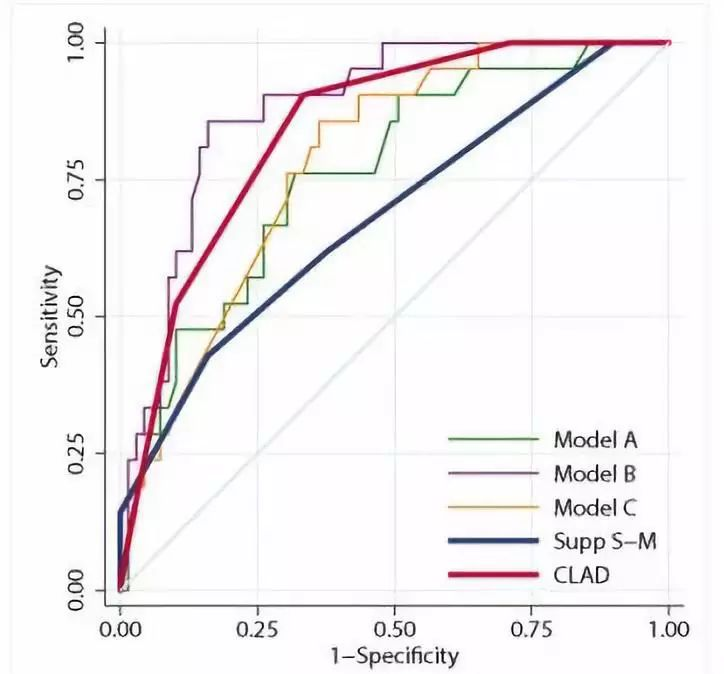

研究结果表明,与补充Spetzler-Martin分级(supp S-D分级)比较(图1),CLAD分级量表对切除近皮质脊髓束AVM的术后运动功能损伤的预测准确度高于supp S-D分级(AUC=0.84比0.68;P=0.023)。NCD越小、CCL越低与近皮质脊髓束AVM切除术后永久性运动功能损伤发生率越高显著相关。根据NCD、CCL、患者年龄以及弥漫型AVM的权重制定的CLAD分级量表预测近皮质脊髓束AVM切除术后运动功能预后具有准确度高的特点(图2),可作为术前风险评估及手术病例选择的有效工具。

图1. ROC分析图。Model A、B、C、Supp S-M和CLAD曲线下面积AUC分别为0.76、0.88、0.78、0.84和0.68。